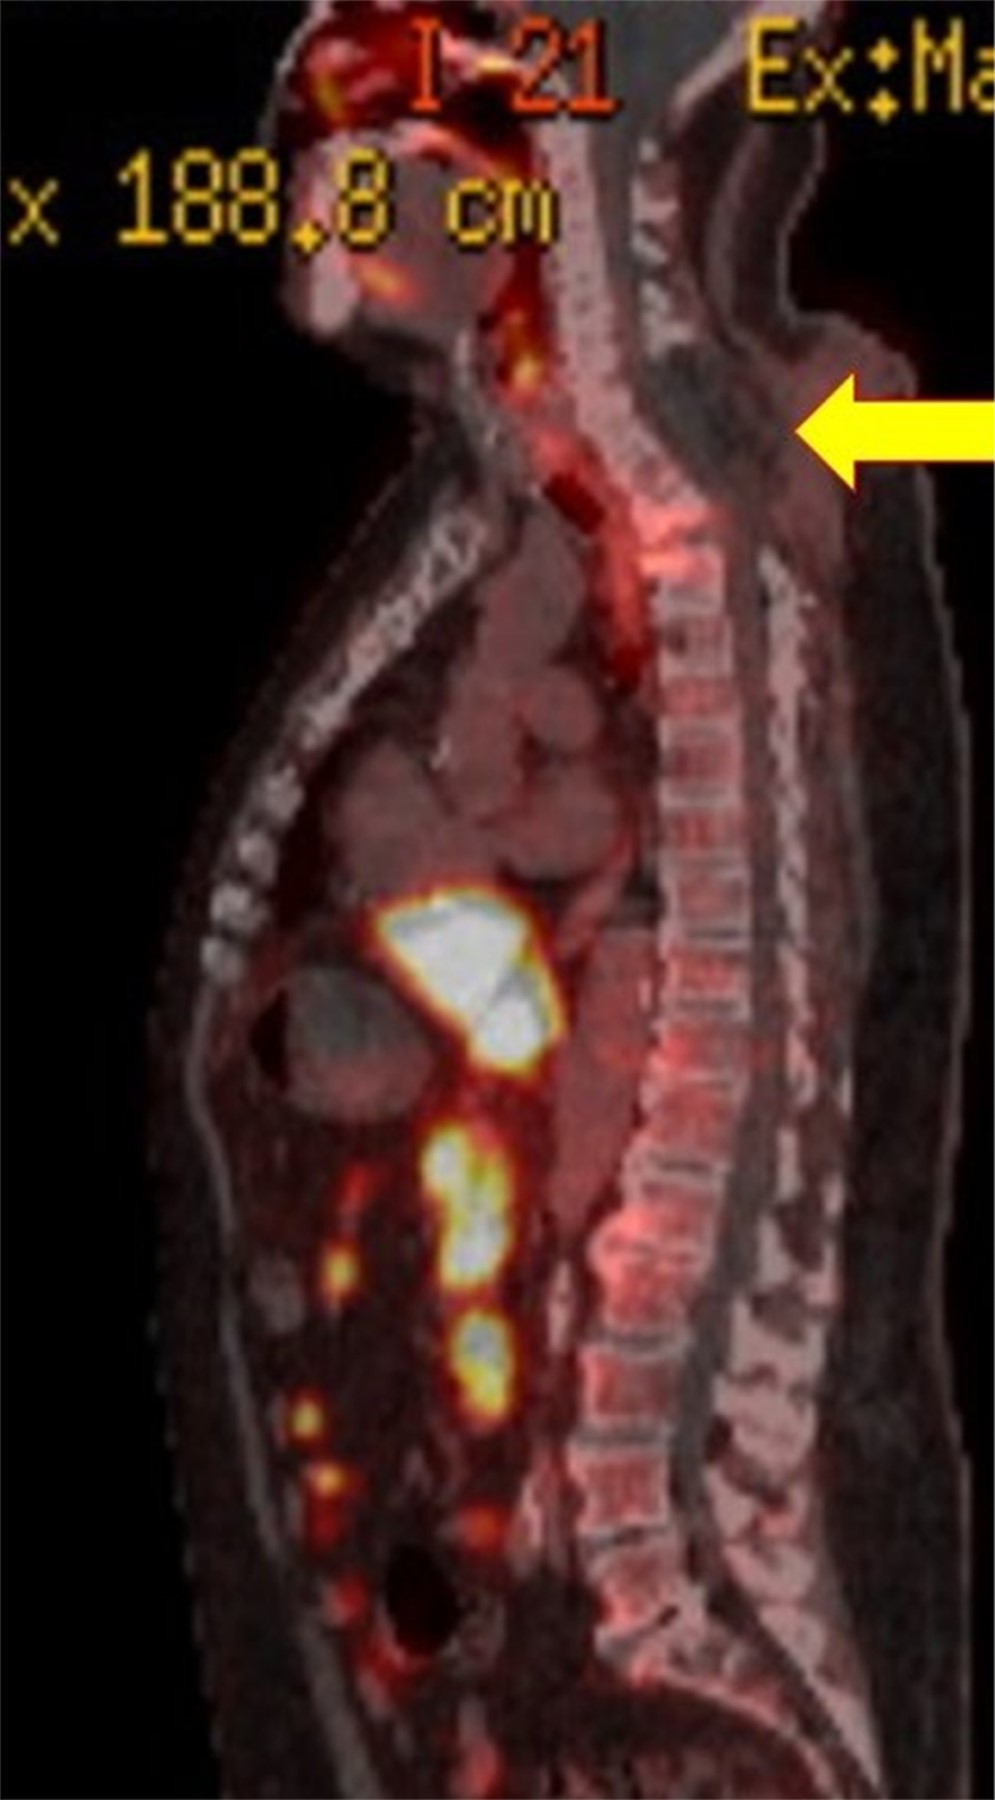

Paciente con espondilodiscitis que presentó deformidad cifótica con compromiso neurológico a nivel torácico superior, quien fue tratado con un nuevo abordaje torácico anterior infraclavicular derecho, como nueva técnica quirúrgica alternativa. Varón de 72 años con deformidad en cifosis secundaria a espondilodiscitis T2-T3 ASIA "C", tratado con instrumentación cervicotorácica posterior C5 a T6 y abordaje anterior transtorácico infraclavicular derecho con colocación de cilindro expandible. Dentro de la revisión bibliográfica realizada en los buscadores no se encontraron técnicas similares a la descrita en este artículo. Dada la complejidad del abordaje quirúrgico, esta nueva técnica se describe como una nueva forma de acceder a la columna torácica superior, demostrando que el abordaje torácico anterior infraclavicular derecho es una nueva alternativa para acceder a la columna torácica superior desde T1 a T4.

Figura 1